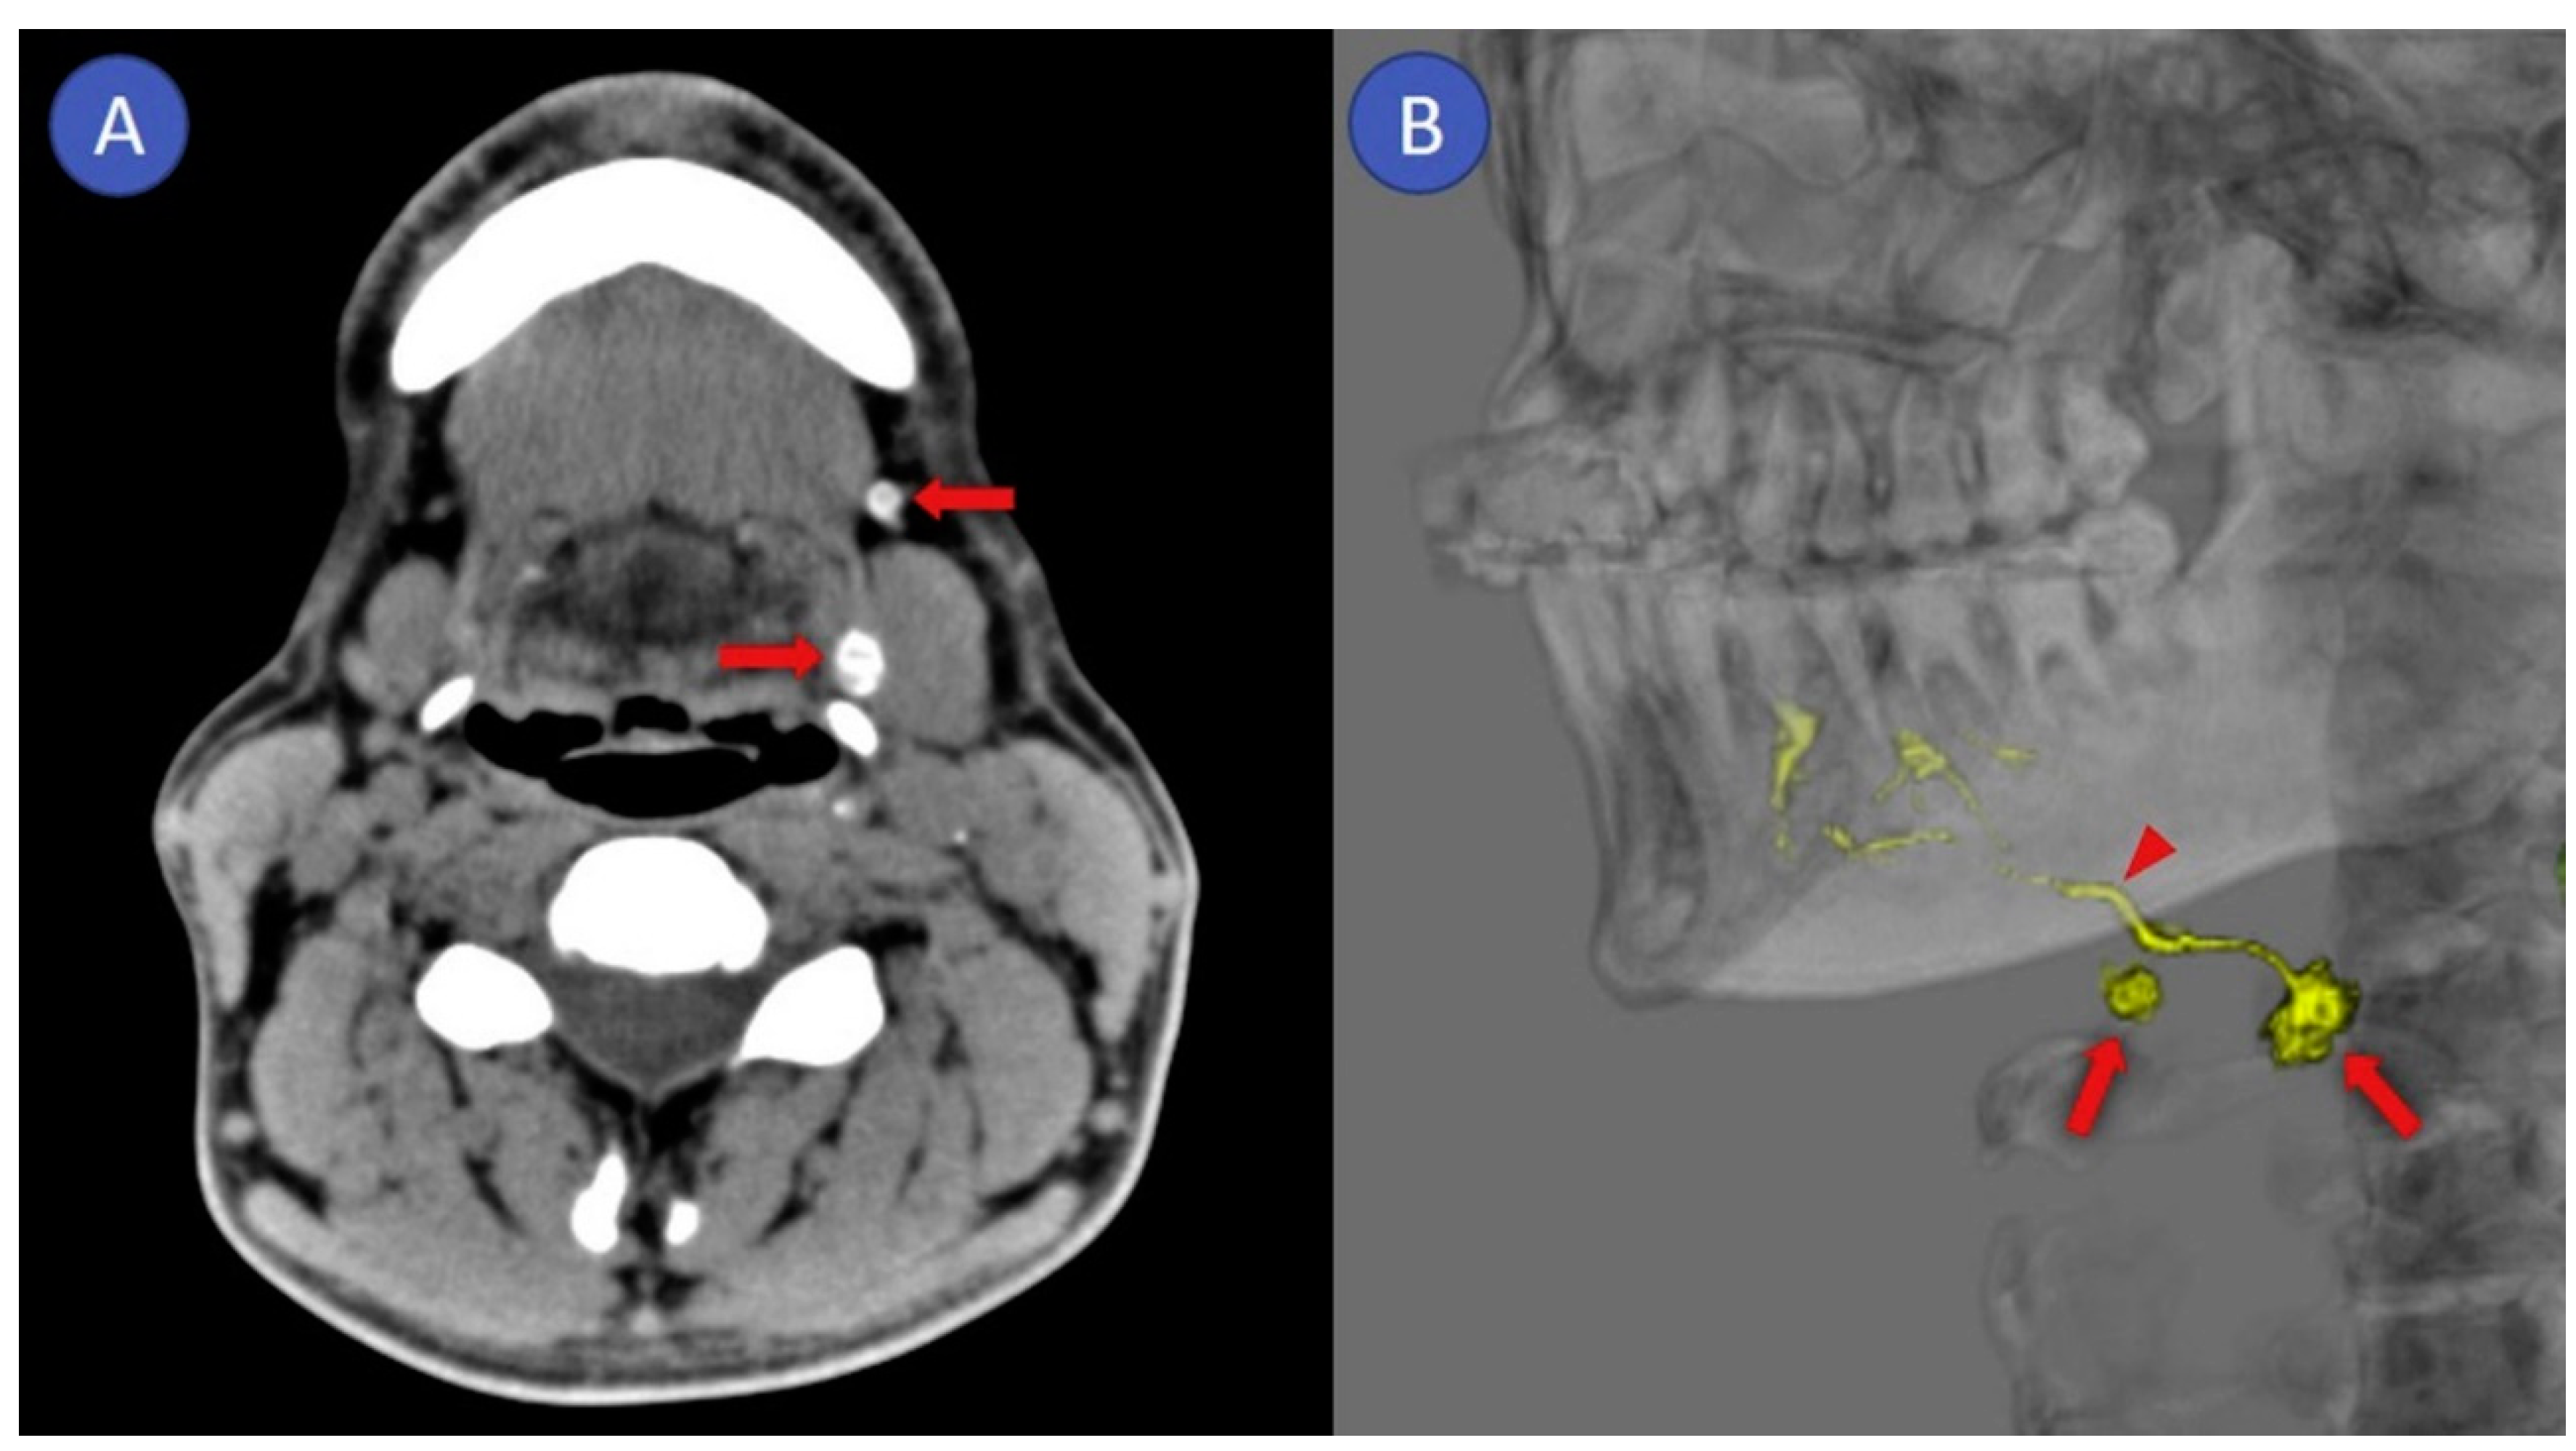

2.2. CT Lymphography

3.2. CT Lymphography

4.2. CT Lymphography